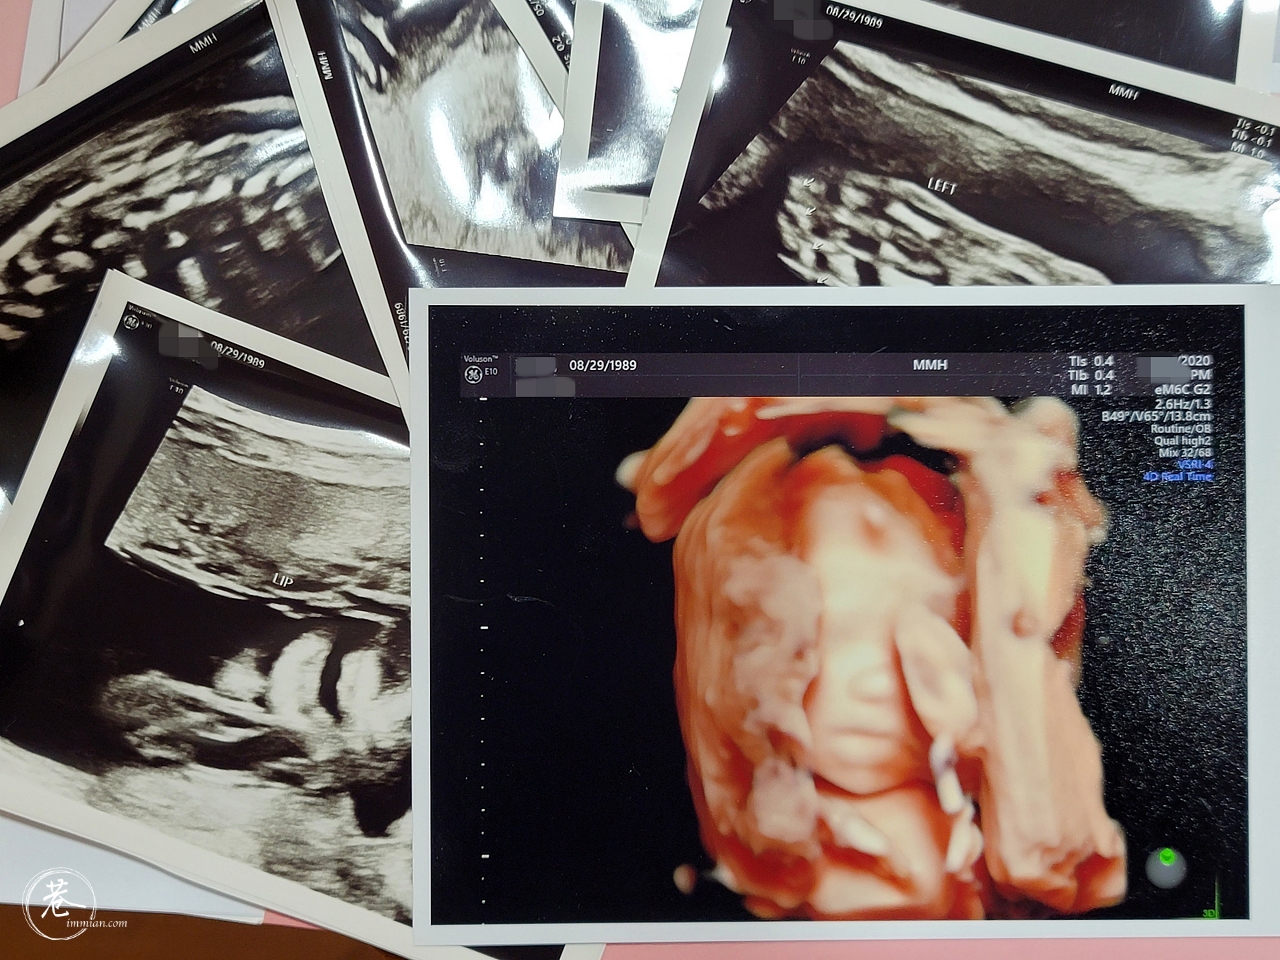

幸好熬過 20 週之後,暈眩情況好了、膀胱炎好了、感冒也好了,終於正式進入比較舒適的懷孕中期了,接下來是 22 週的高層次超音波還有糖水檢測,希望都能順利通過,寶寶健健康康那就最好了!